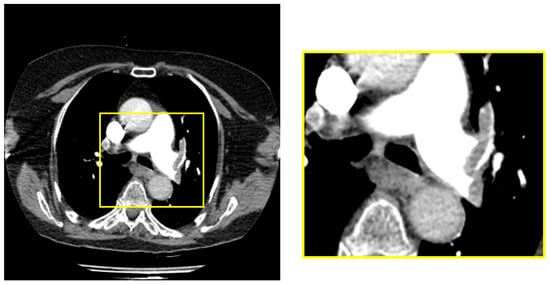

2.4. Enhanced Mask R-CNN Architecture